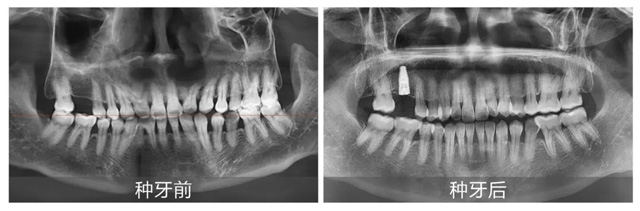

易华波医生对本次手术进行了简单总结:胡女士的手术相对简单,但即便如此,每一例种植牙手术前期方案的制定都至关重要。他表示,种植牙不仅仅是替换缺失牙齿,还要考虑口腔未来的整体健康和咀嚼功能的恢复,在手术过程中,我们需要确保种植体的位置、角度以及与周围牙齿的间隔,力求为每一位顾客带来最优质的诊疗体验。